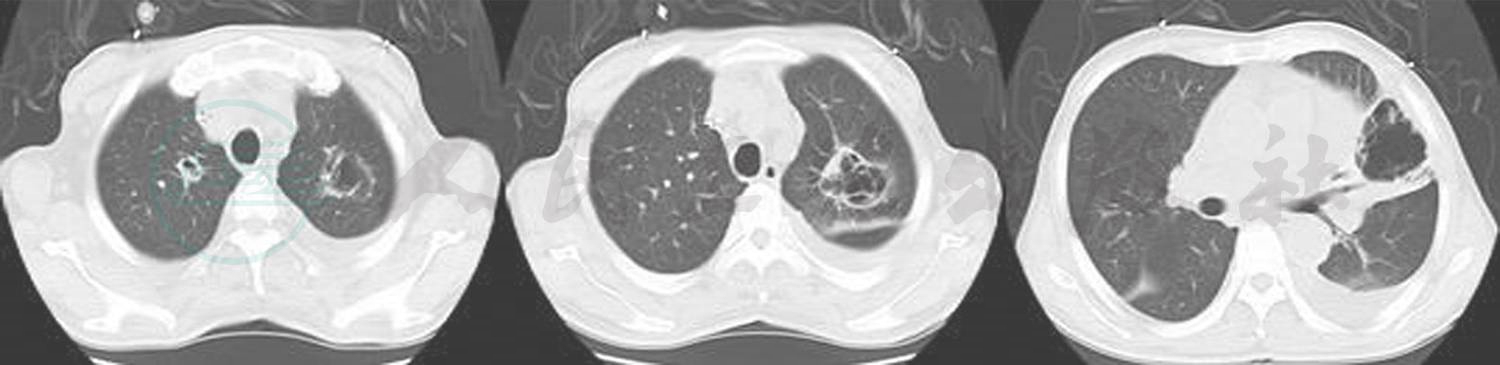

后经微生物科鉴定为根霉。明确致病原后继续两性霉素B治疗,逐渐停用其他抗生素,病人咳嗽、胸闷等症状逐渐缓解,营养状况改善,血糖控制理想。2015年2月2日复查肺CT提示空洞逐渐闭合、吸收(图5)。

图5 2015-2-2胸部CT